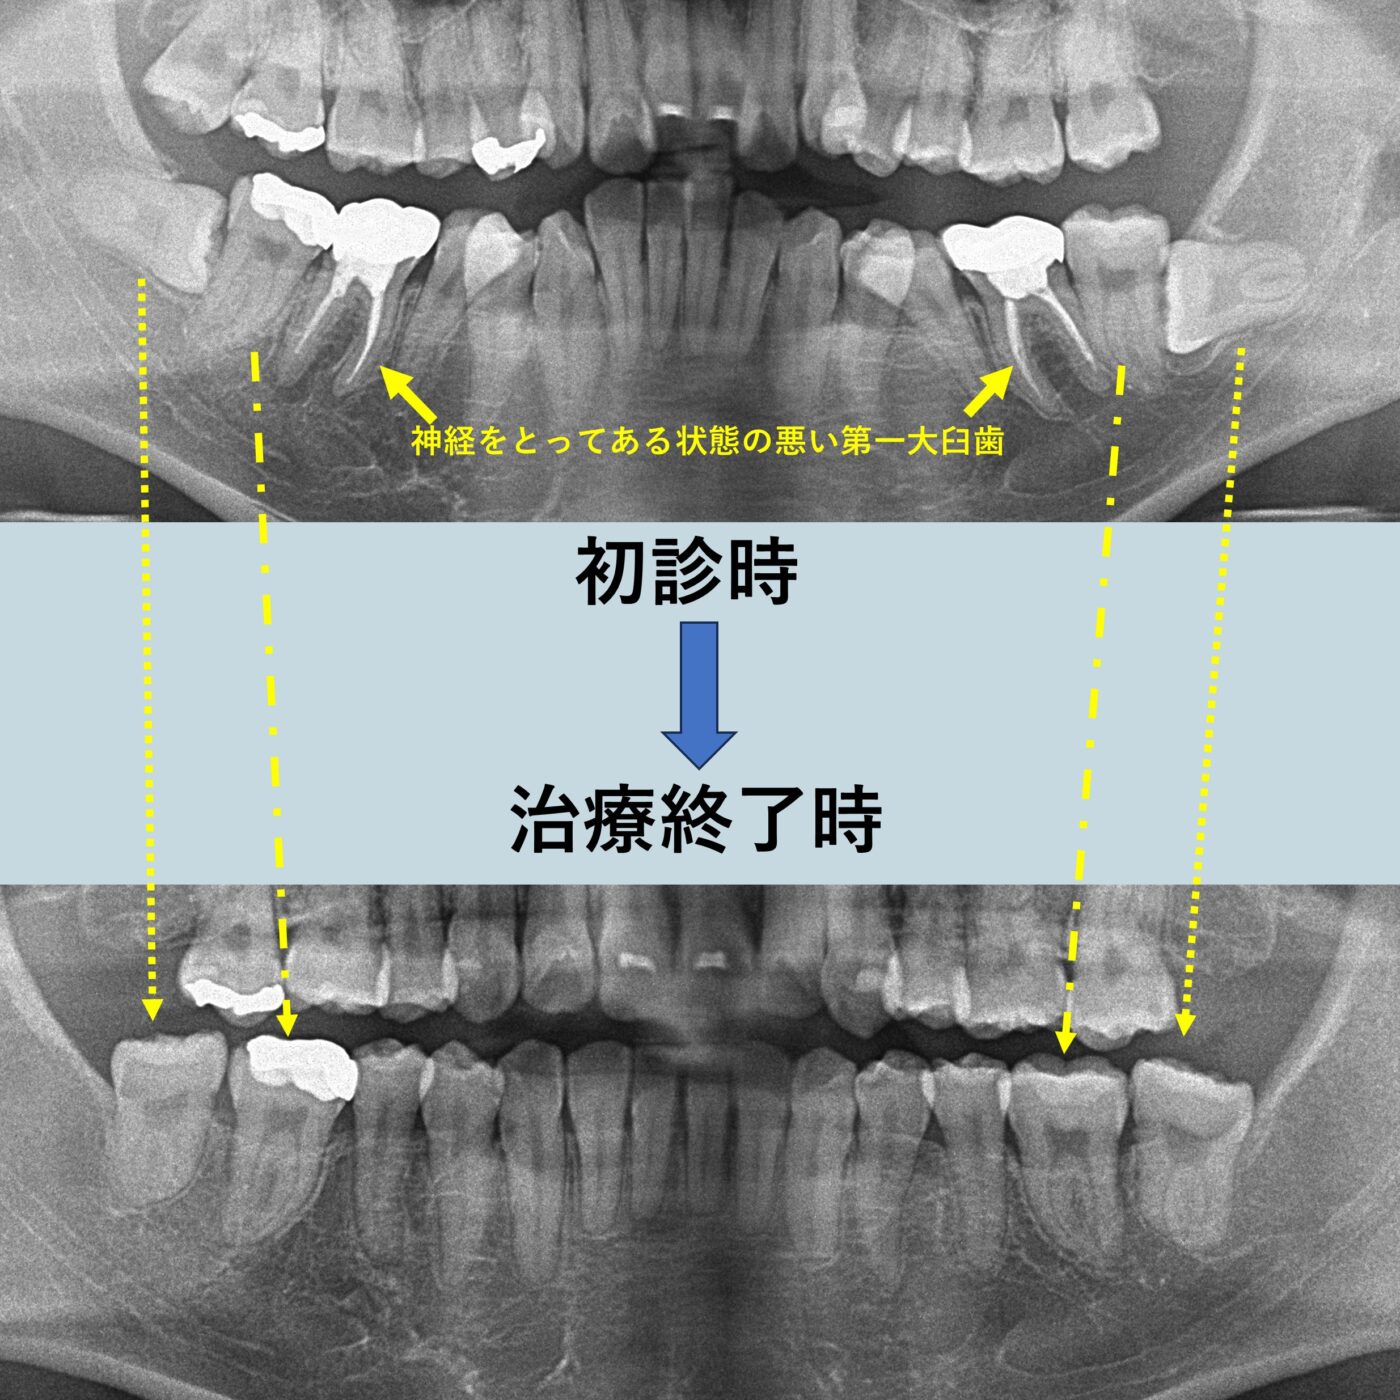

24歳女性:予後不良な奥歯を抜歯して真横になっていた親知らずを利用して並べたケース

今回のケースでは著しい上顎前突を呈していたことから、歯科矯正用アンカースクリューを利用して上顎の前歯をできる限り後方移動させることにしました。また、患者さまの希望があり神経を抜いてある状態の悪い奥歯を抜歯して、真横になって埋まっている親知らずを引っ張り出してかみ合わせに参加させることにしましたが、この方針ですと4年ほどの治療期間がかかる可能性がありました。しかし、顎間ゴムの使用協力もよく、真横になっていた親知らずも素直にまっすぐに修正できたことから3年4か月という短期間で治療終了となりました。 ※ 真横になっている親知らずを引っ張り出す装置をつけるために口腔外科にて開窓牽引を行っています。